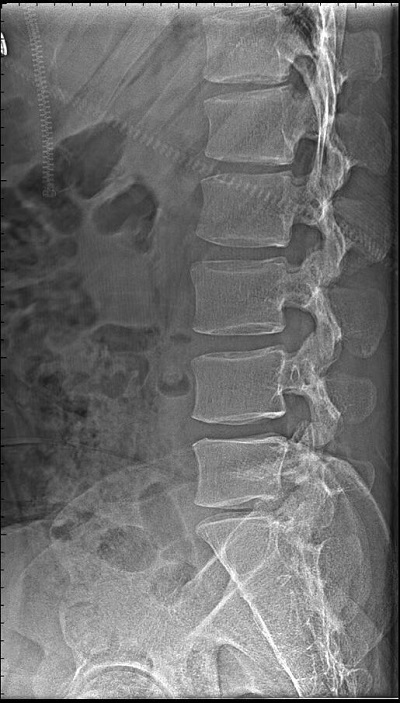

DR影像簡(jiǎn)介:直接數(shù)字平板X線成像系統(tǒng),應(yīng)用于:臨床醫(yī)學(xué),影像部份能夠上下、左右移動(dòng),對(duì)全身骨骼、心血管、呼吸系統(tǒng)、五官、神經(jīng)系統(tǒng)進(jìn)行高質(zhì)量拍片。

DR通俗來(lái)講就是數(shù)字化的X射線,X光是傳統(tǒng)的影像學(xué)檢查手段,主要用于一些的初步篩查。與傳統(tǒng)的X線機(jī)相比DR的輻射非常小,還可以進(jìn)行后期處理分析。

優(yōu)點(diǎn):作用廣、快捷、價(jià)廉。如呼吸科明確是否有肺部病變,骨科用來(lái)判斷是否骨折、消化科查看是否有腸梗阻等都可以用X光檢查。

缺點(diǎn):受制于深淺組織的影像相互重疊和隱藏,有時(shí)需要多次多角度拍攝X光片才能看清。DR設(shè)備有哪些使用注意事項(xiàng)?DR是一種十分與相當(dāng)貴重的儀器,在日常的生活應(yīng)用中還需要結(jié)合其實(shí)際的使用性能進(jìn)行良好的維護(hù)和保養(yǎng),并結(jié)合其實(shí)際的情況分析故障出現(xiàn)的原因。具體而言,應(yīng)該注意以下問(wèn)題: